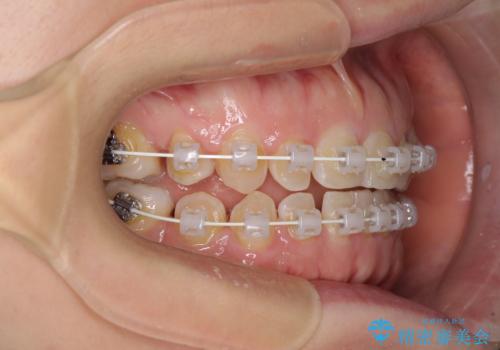

隙間の空いた歯列とボロボロの乳歯 インプラント治療と矯正治療

- 隙間の多い歯列や傾斜した奥歯、むし歯の酷い残存乳歯を気にして来院された患者様です。

歯列はワイヤー矯正にて改善することとしましたが、上下歯列にも隙間があったので、舌の突出癖を改善するトレーニングを徹底的に行うこととしました。

傾斜した下顎の奥歯は、矯正治療にてまずは歯軸を改善させ、隙間が閉じられるようであればそのままに、閉じられないようであればインプラント治療を行うこととしました。

上顎のむし歯の酷い残存乳歯は抜歯をし、矯正治療の途中でインプラントを埋入、矯正治療後に補綴治療を行うこととしました。